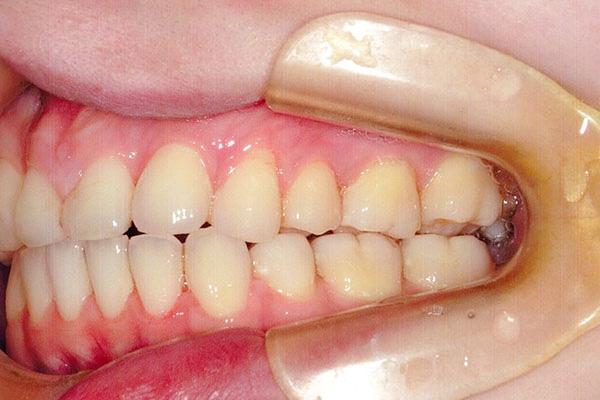

3年2ヶ月後